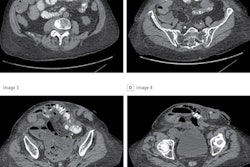

Example of body composition analysis of an abdominal CT slice with subcutaneous fat in green, skeletal muscle in red, and visceral fat in yellow. Image and caption courtesy of Dr. Kirti Magudia, PhD, and the RSNA.The researchers next used the algorithm to retrospectively determine body composition areas for all outpatient abdominal CT exams performed at Partners HealthCare in Boston in 2012. After subjects with major cardiovascular disease or cancer were excluded, a total of 12,128 patients were included in the study.